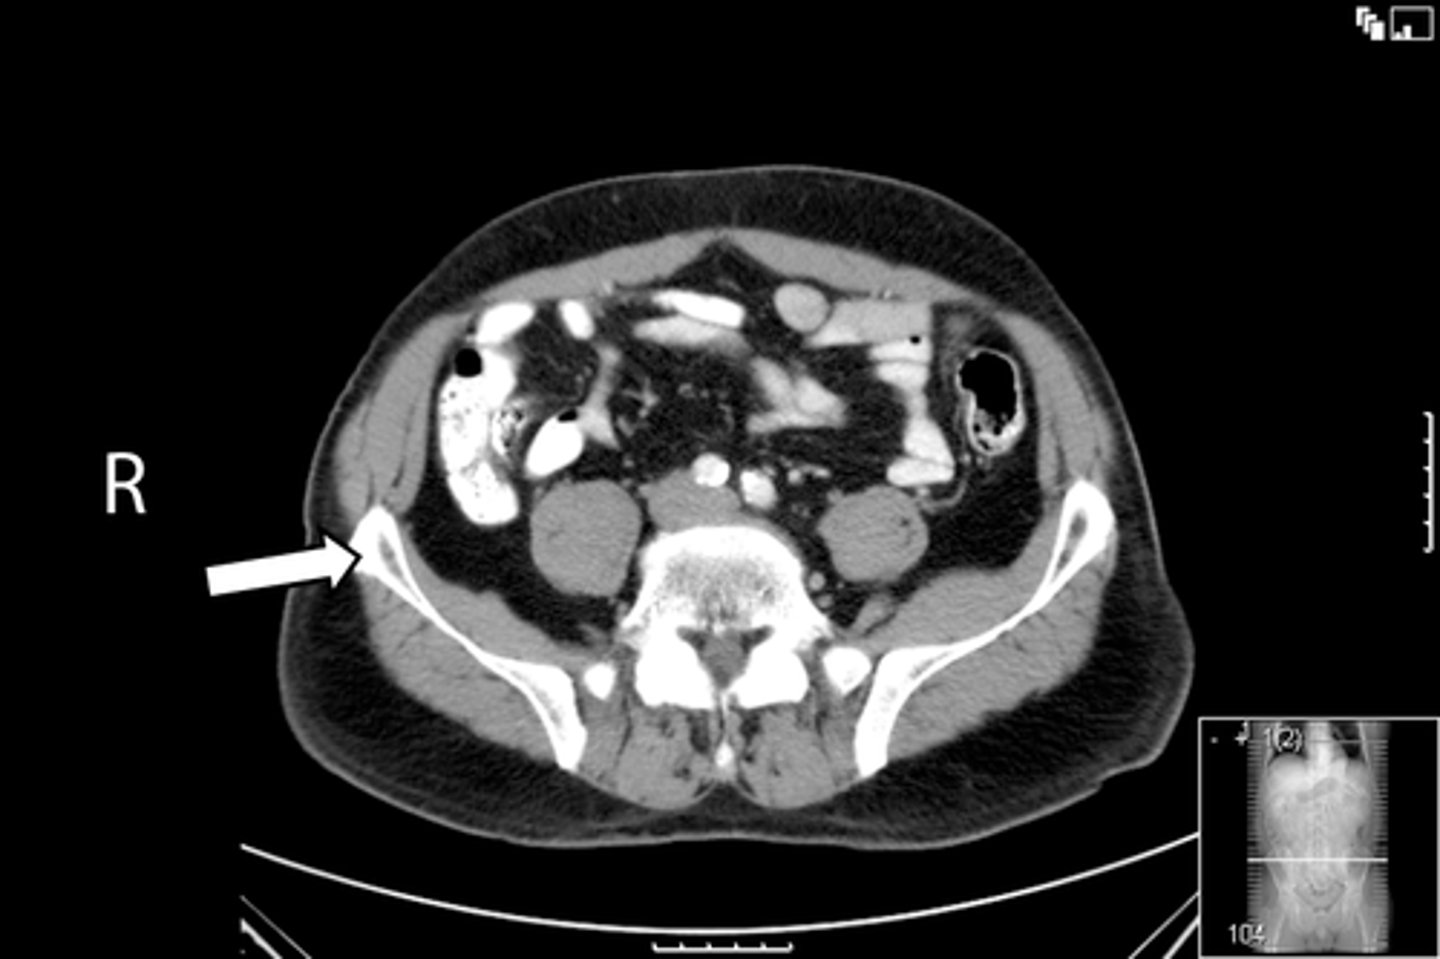

Axial bony pelvis CT

What is the image?

38

New cards

L acetabulum

What is indicated in the image?

<p>What is indicated in the image?</p>

39

L femoral head

40

L piriformis muscle

41

R femoral head

42

R piriformis muscle

43

R acetabulum (posterior part)

44

Sacrum